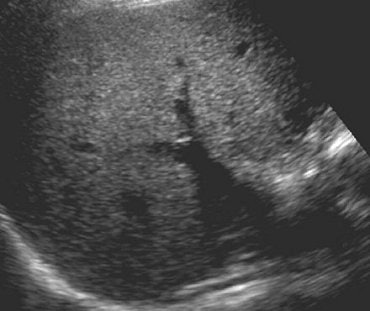

| Above, axial control sonogram obtained at level of injury does not show any parenchymal abnormality. Below, axial contrast-enhanced sonogram reveals liver injury as deep hypoechoic area (between arrows) surrounded by enhanced hyperechoic parenchyma. |

| Poletti PA, Platon A, Becker CD, Mentha G, Vermeulen B, Ubhler LH, Terrier F, "Blunt Abdominal Trauma: Does the Use of a Second-Generation Sonographic Contrast Agent Help to Detect Solid Organ Injuries?" (AJR 2004; 183:1293-1301). |